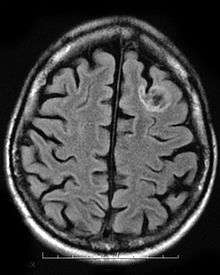

Oligodendroglial tumors manifest in glial cells, which are responsible for supporting and protecting nerve cells in the brain. The tumor develops over oligodendrocytes and is usually found in the cerebrum around the frontal or temporal lobes. The tumors can either grow slowly in a well-differentiated manner delaying the onset of symptoms, or they can grow rapidly to form an anaplastic oligodendroglioma. The symptoms for this type of tumor include headaches and visual problems. Additionally, blockage of ventricles could cause buildup of cerebral spinal fluid resulting in swelling around the tumor. The location of the tumor may also affect the symptoms since frontal lobe tumors can cause gradual mood or personality changes while temporal lobe tumors result in coordination and speech problems.[10]